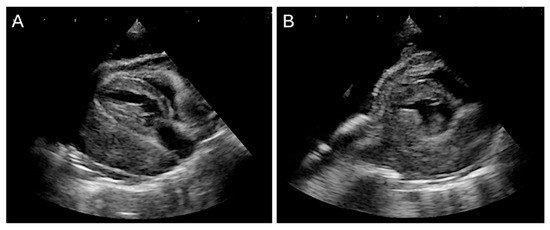

Veterinary cardiology has become a permanent fixture, both in the way of services provided by general practitioners, and also in specialized centers, which are being established in growing numbers around the world. Acquired heart disease, which develops and progresses with age, accounts for the vast majority of cardiac cases. They are also the subject of greatest interest to researchers, due to the prevalence and difficulties encountered during their treatment. Among them, the most common are myxomatous mitral valve disease in small-breed dogs, dilated cardiomyopathy in large-breed dogs and hypertrophic cardiomyopathy in cats. In contrast, congenital heart defects, which are significantly less common, can pose considerable diagnostic challenges and be cumbersome in terms of selecting the optimal treatment protocol. Due to the rapidly developing branch of interventional cardiology, including minimally invasive procedures, a growing number of defects, such as patent ductus arteriosus, pulmonic stenosis, atrial septal defects or ventricular septal defects, can be successfully addressed by surgical methods. In many cases, such treatment results in a complete recovery, which positively affects the rest of the animal's life. With the use of advanced diagnostics, such as 3D and 4D transesophageal echocardiography, cardiac magnetic resonance imaging (MRI), and cardiac computed tomography (CT), the characteristics of acquired and congenital defects and their complexities can be assessed very accurately, favoring the selection of optimal treatment methods, as well as allowing the determination of possible strategies for surgery. Thanks to this comprehensive approach, veterinary cardiology services in many countries around the world have achieved incredibly high standards of care.